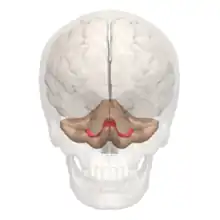

![]() | ||

![]() Cerebelo en púrpura. Sección sagital de un encéfalo en una RMN. | ||